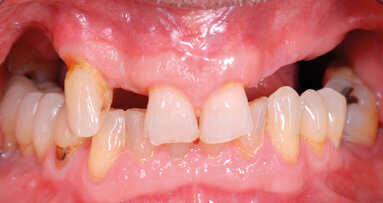

Lo scopo di questo articolo è presentare una alternativa terapeutica al rialzo di seno mascellare nei casi in cui si verifichi una estesa pneumatizzazione dei seni mascellari nella zona del primo premolare.

Nelle riabilitazioni implanto-protesiche del mascellare atrofico esistono delle alternative alla chirurgia di elevazione del seno mascellare che devono ...